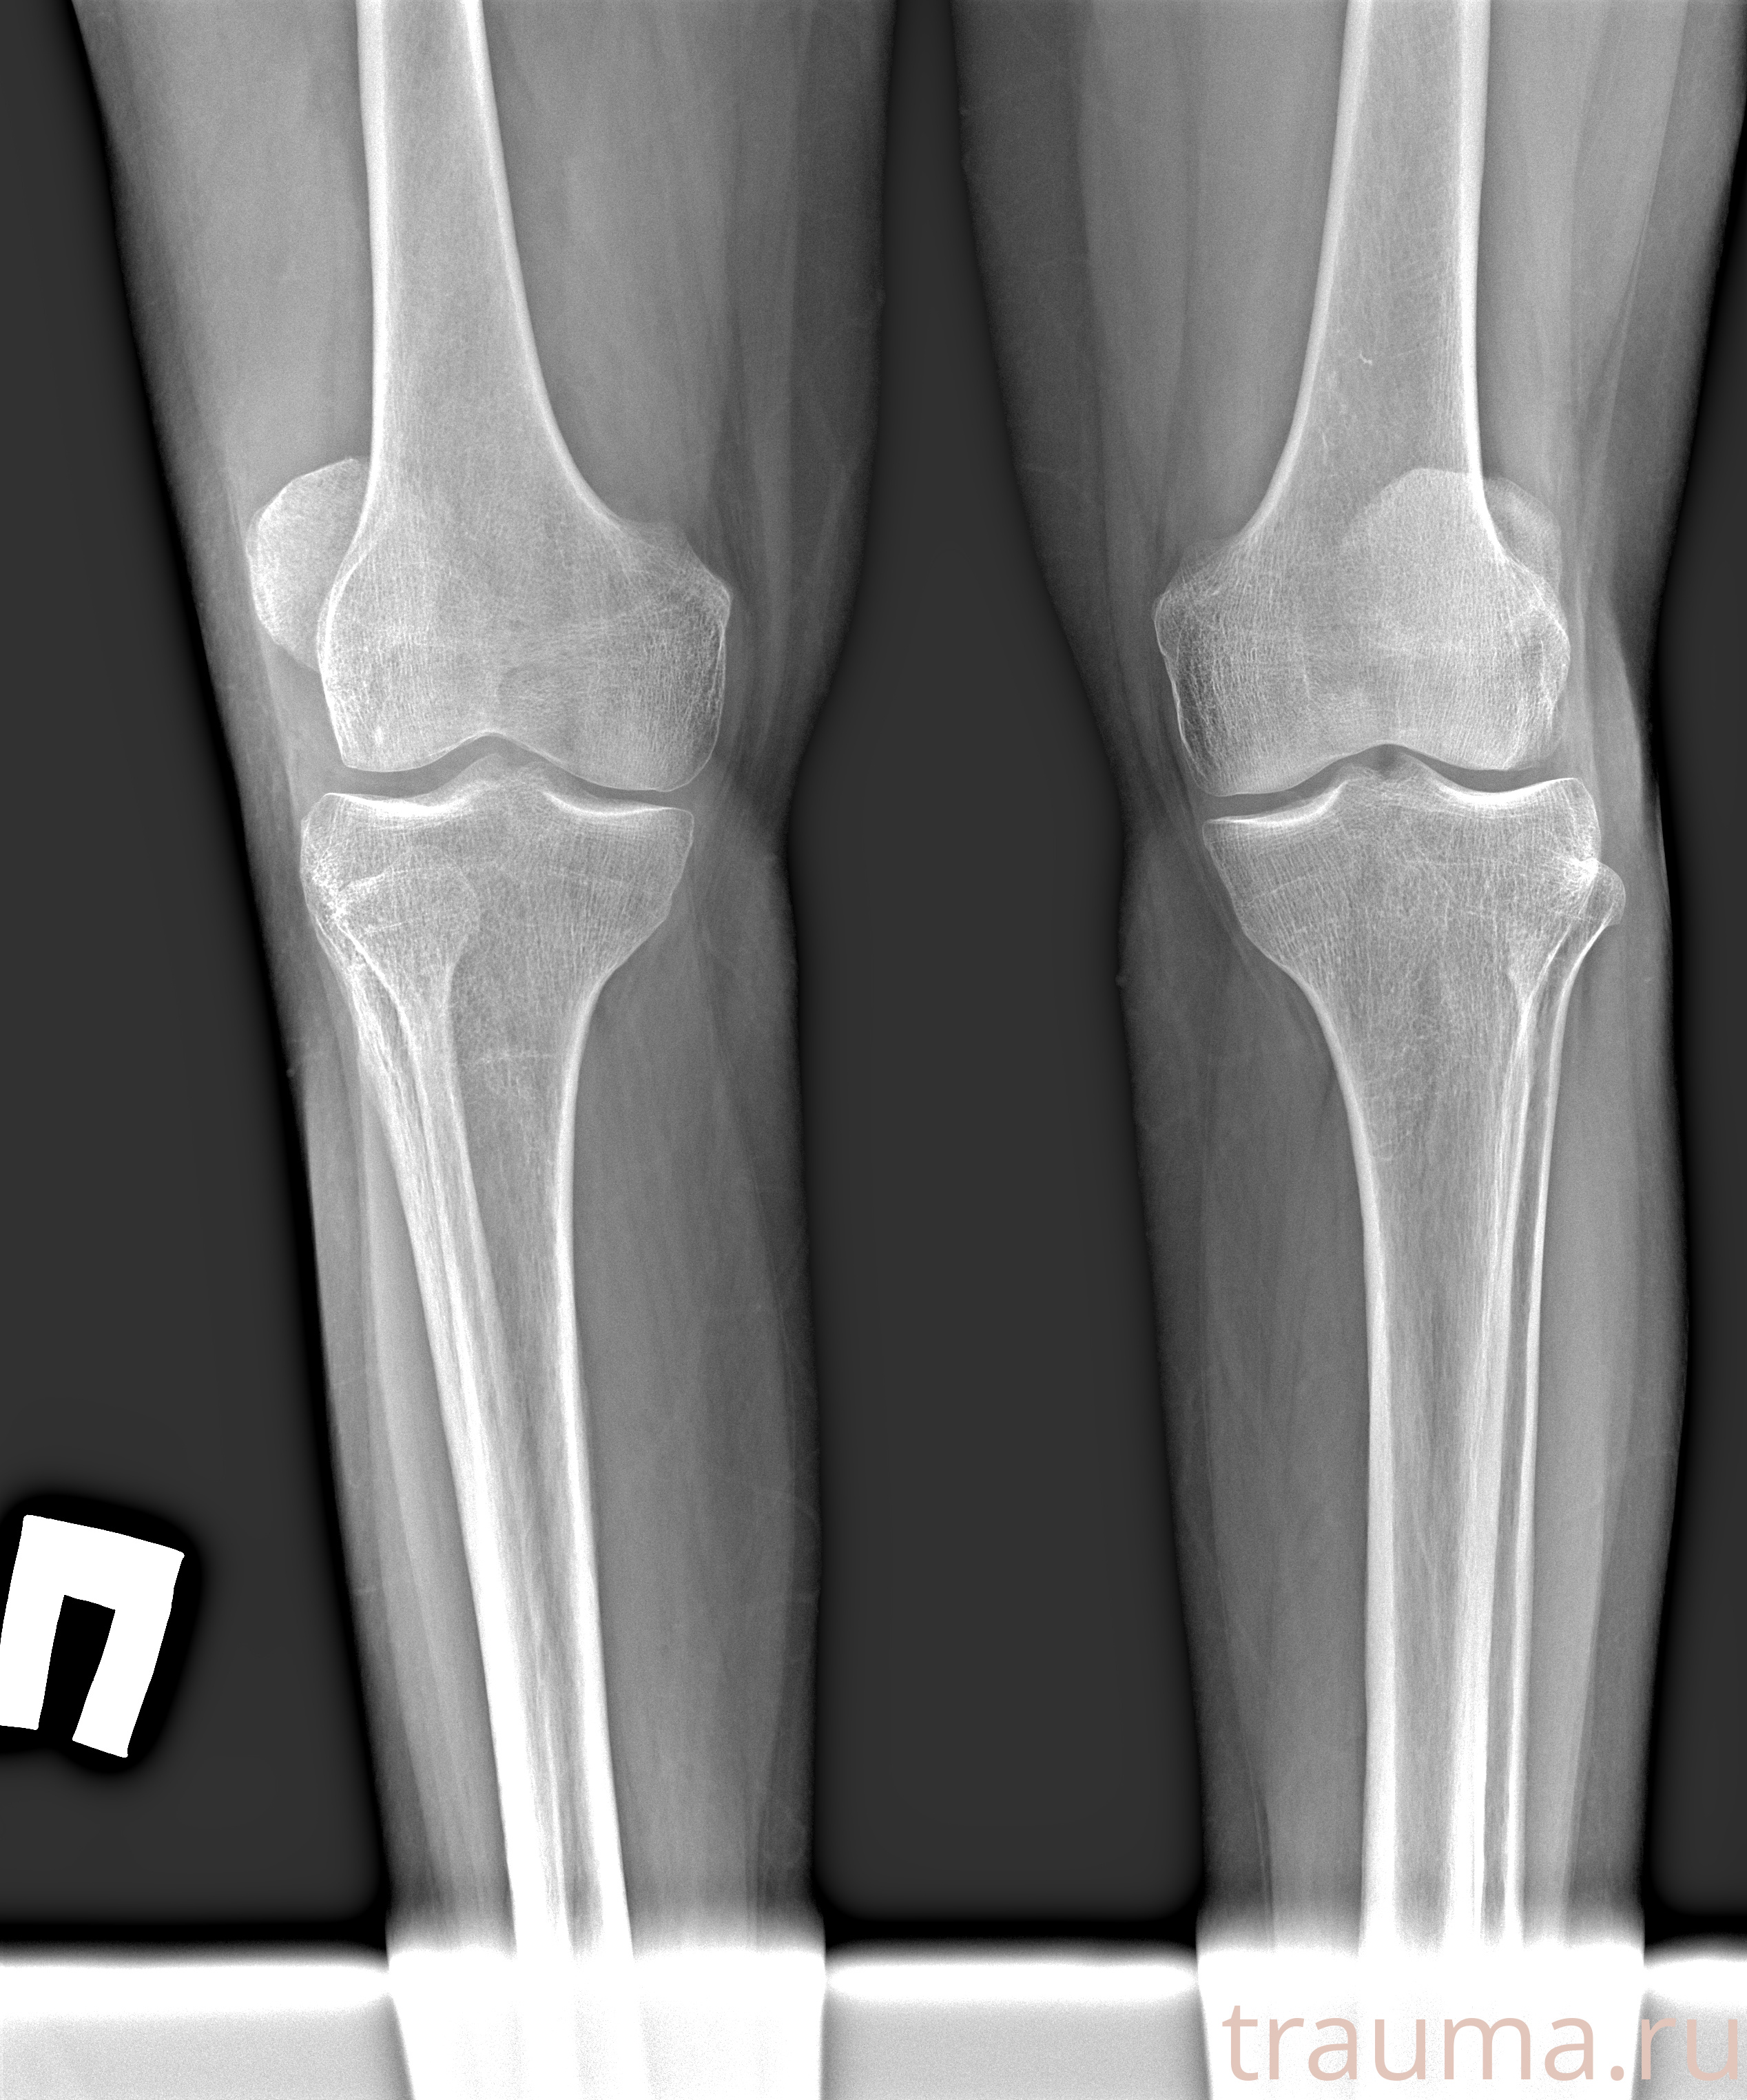

Рентгенограммы

Рентген на дому: по вашему адресу приезжает врач-рентгенолог, травматолог-ортопед с мобильным рентгеновским аппаратом, проводит диагностику травмы или заболевания, делает необходимые рентгенограммы, дает рекомендации по дальнейшему лечению. Получить качественные снимки в домашних условиях возможно благодаря уникальной методике, разработанной МосРентген Центром для института  Склифосовского